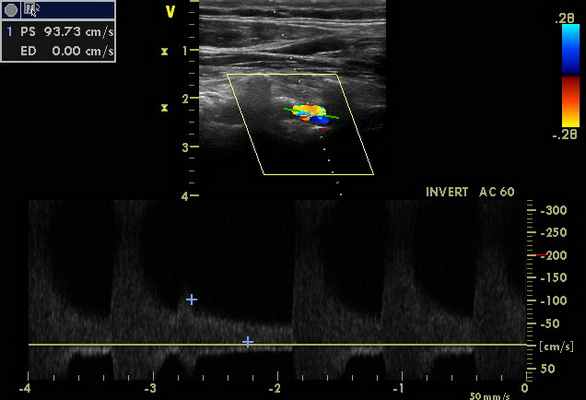

Признаки стенозов в V 2 сегментах позвоночных артерий с обеих сторон - по спектральным характеристикам - 75-85%, (правая ПА - на рис. 3). На рис. 4 – признаки субокклюзии – окклюзии ОСА слева (состояние после стентирования и эндартерэктомии - 2011 г.).

При транскраниальном исследовании - признаки коллатерального кровотока (рис. 6), с признаками повышение ЛСК по ЗМА с обеих сторон, в т. ч. на фоне стенозирования от 50% (рис. 5 - ЗМА справа), с регистрацией ретроградного кровотока по обеим глазным артериям (рис. 7 - правая ГА).